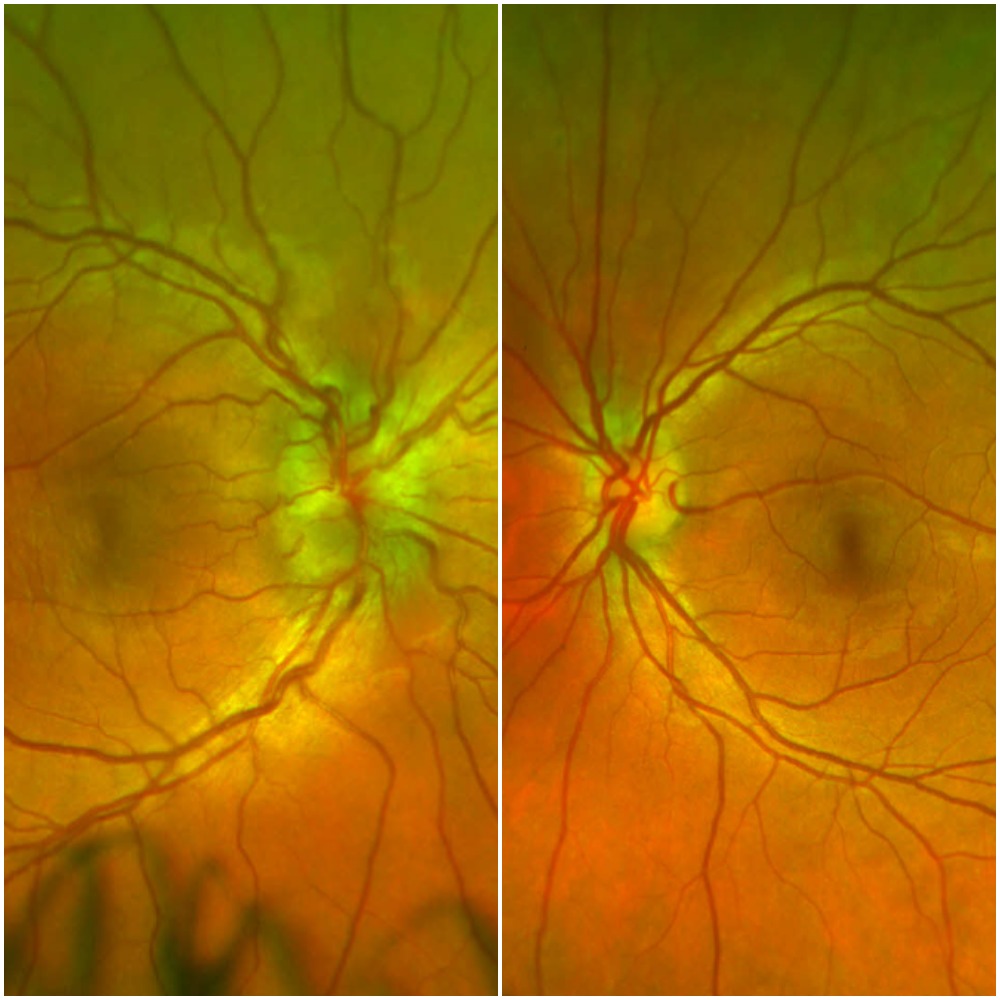

A maxillofacial CT showed right preseptal cellulitis with a small abscess. Wound cultures from an incision and drainage grew MRSA sensitive to TMP/SMX, which began resulting in improved periorbital swelling and decreased pain. Despite this improvement, the patient continued to complain of decreased visual acuity in her right eye that eventually progressed to both eyes on hospital day four. Ophthalmology was consulted and a dilated fundoscopic exam revealed bilateral, asymmetric optic disc swelling and optic papillitis. An orbital MRI revealed bilateral optic neuritis. A lumbar puncture was subsequently performed that revealed an opening pressure of 14 cmH2O, glucose 51 mg/dL, protein 43 mg/dL, nucleated cell count 2 cells/cumm, and a non-reactive VDRL. Serum studies demonstrated an RPR titer 1:128, reactive T. pallidum antibody, and reactive FTA-ABS, leading to the diagnosis of isolated ocular syphilis. The patient was started on aqueous penicillin G at 4 million units IV q4h for 10 days and penicillin G benzathine 2.4 million units IM weekly for 3 weeks. The patient completed three days of treatment with improved symptoms before leaving the hospital against medical advice.

Discussion: Isolated ocular syphilis is an uncommon presentation of neurosyphilis, especially among HIV-negative patients. Although classically associated with syphilitic meningitis, ocular syphilis can present independently during any stage of syphilis. It can also develop occultly, as was seen in our patient, whose diminished visual acuity was initially attributed to her recent trauma. Ocular syphilis most commonly presents as posterior uveitis and panuveitis. The most common presenting symptoms include diminished visual acuity, eye redness, and blurry vision. The treatment for neurosyphilis and ocular syphilis is 18-24 million units of Penicillin G daily for 10-14 days.